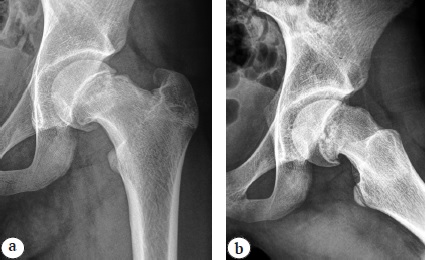

По рентгенограммам в переднезадней проекции и в проекции Лауэнштейна с двух сторон определялись значения проекционного шеечно-диафизарного угла (ШДУ), проекционного эпифизо-диафизарного угла (ЭДУ), эпифизарного угла (ЭУ), исключались признаки частичного и полного синостозирования на уровне эпифизарной зоны роста. На стороне деформации определяли значения углов смещения эпифиза кзади и книзу, подтверждали наличие положительного симптома «сегмента», костного выступа на передней поверхности шейки бедренной кости, отсутствие смещения эпифиза с контралатеральной стороны (рис. 2).

Рис. 2. Рентгенограммы правого тазобедренного сустава в переднезадней проекции (а) и в проекции Лауэнштейна (b) пациентки 14 лет 9 мес. перед операцией: отсутствие признаков синостозирования на уровне эпифизарной зоны роста, положительный симптом «сегмента», костный выступ на передней поверхности шейки бедренной кости

Угол смещения эпифиза кзади рассчитывался по разнице ЭУ в суставе без смещения (индивидуальная норма) и в суставе со смещением, угол смещения книзу — по разнице ШДУ и ЭДУ в суставе со смещением.